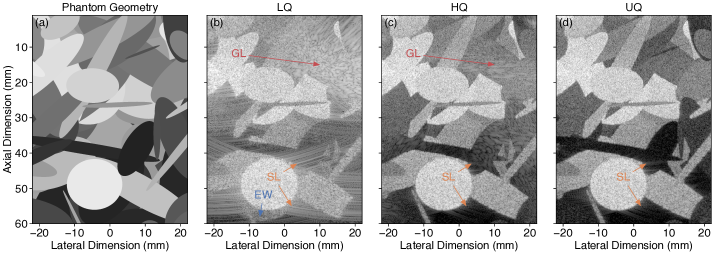

Representations of a simulated dataset sample are shown in Fig. 3, highlighting the differences in diffraction artifacts between LQ, HQ, and UQ configurations [Fig. 3, 3 and 3]. The image obtained from the UQ configuration is free from GL artifacts, while the HQ image still suffers from them (although significantly reduced compared with LQ). Both HQ and UQ configurations result in images free from EW artifacts and with SL artifacts significantly reduced compared with LQ. Due to the spatial dependency of the imaging configuration PSFs (Supplementary Material, Section S-II.1), the spread of these artifacts is also spatially dependent.

Refer to caption\phantomsubcaption\phantomsubcaption\phantomsubcaption\phantomsubcaption

Fig. 3: B-mode image representations (989898-dB/dividedecibelabsent\mathrm{dB}\text{/} range) of a simulated dataset sample: 3 the phantom mask composed of elliptical inclusions; images reconstructed using each imaging configuration considered (Table 1), namely 3 \glsxtrfulllq configuration, 3 \glsxtrfullhq configuration (i.e., gold-standard image for the physical transducer array), and 3 \glsxtrfulluq configuration (i.e., gold-standard image for the spatially oversampled virtual version of the transducer array, considered as ground-truth). Some zones dominated by \glsxtrfullgl, \glsxtrfullsl, and \glsxtrfullew artifacts are highlighted by colorized arrows and associated annotations.